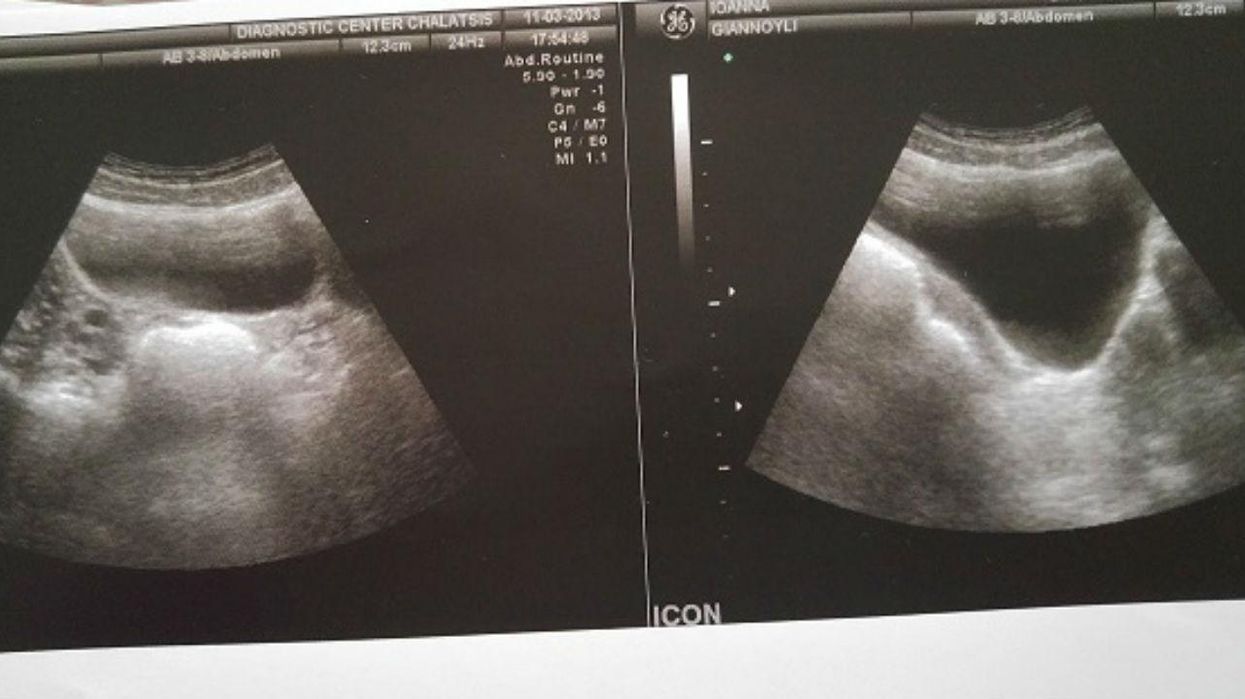

Photo: Joanna Giannouli

Joanna Giannouli, was born with Rokitansky syndrome, which means she has no cervix, no womb and (until fairly recently) no upper vagina.